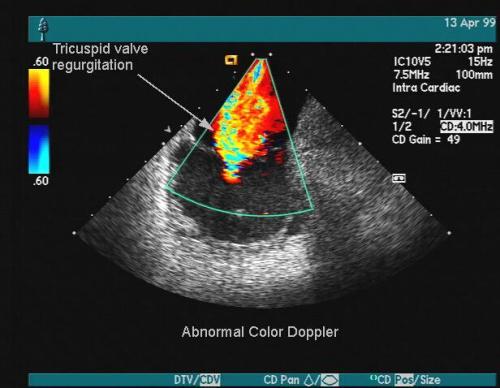

心脏 B 超:采用彩色多普勒超声诊断仪(日立 ALOKA SSD-210 型号)对患者进行心脏 B 超诊断。患者处于安静、全身放松的状态下,取其平卧位,对患者胸骨旁左心室长轴切面行二维超声扫描,根据检测数据计算左心室 EF 值,测算峰值速度比率。

临床中诊断高血压性心脏病常用方法有心电图、心脏 B 超检查,心电图是一种无创伤检查方法,具有操作便捷的优势。心脏 B 超是一种新型诊断方法,其无发射性、损伤性,可重复使用,有效降低了诊疗成本。采用心脏 B 超诊断高血压性心脏病,可以在检测画面中清晰、准确地查看患者心脏等器官,提高是实体感,并贴近临床解剖的脏器结构 [3]。心脏 B 超的诊断原理是将适合强度的超声波通过探头发射,作用于心脏部位,在不对心脏产生任何损伤的情况下,通过超声波将心脏病变情况以图像形式显示,让医务人员可以清楚掌握心脏病变情况,较为心电图检查具有较大的优势。与心电图检查相比,心脏 B 超诊断心脏病具有较高的特异性、敏感性, 通过多普勒扫描仪还可检测心脏的血流情况,判断心脏功能情况,提高诊断的准确性。本次研究结果显示,心脏 B 超检查心肌缺血、左室肥厚劳损、心率(心律)变化检出率高于心电图检查诊断准确率为 90.00%,显著高于心电图检查诊断准确率 62.00%,具有统计学意义(P<0.05)。这与周美华 [4] 研究结果相符,说明心脏 B 超在高血压性心脏病诊断中具有较高的应用价值,能有效提高诊断准确率,为高血压性心脏病临床治疗提供参考。